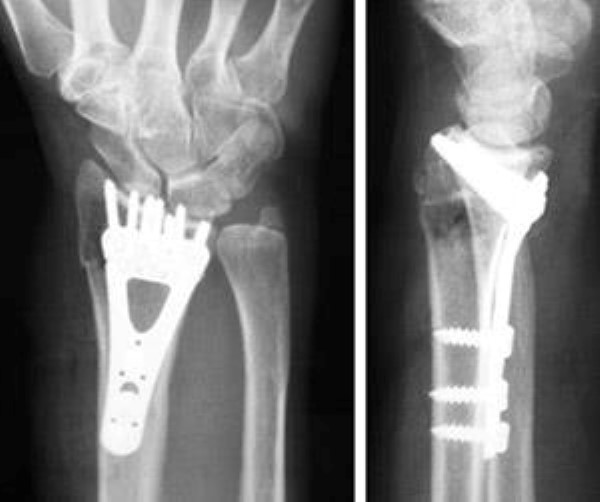

• Plate and screws — This is the most common option for surgical treatment of distal radius fractures.

internal fixation for distal radius fracture

A plate and screws hold the broken fragments in position while they heal.